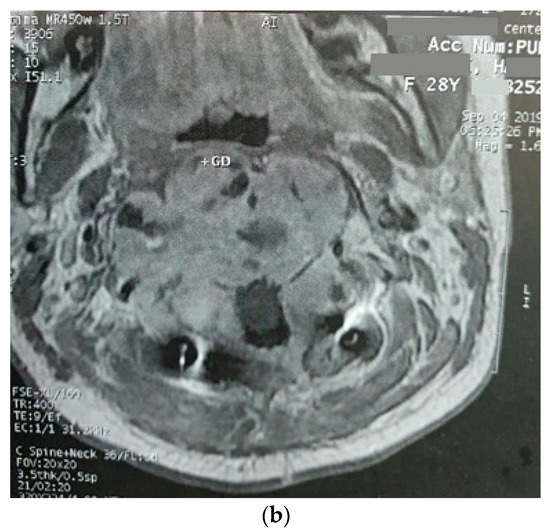

| The current case | 29, female | C2 | CD45, CD43, CD68, S100 | Surgery and radiotherapy | Brain metastasis after 9 months |